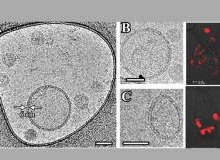

Ученые НИЦ "Курчатовский институт" – ПИЯФ выявили изменения в механизмах регуляции генов, отвечающих за вывод холестерина из жировой ткани, которые говорят о вероятном развитии осложнений при ожирении.